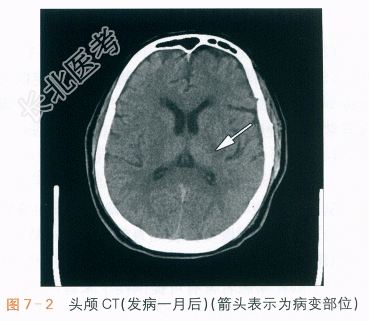

头颅CT(1个月后复查):左侧丘脑-基底节脑出血,较前片吸收减小,如图7-2所示。